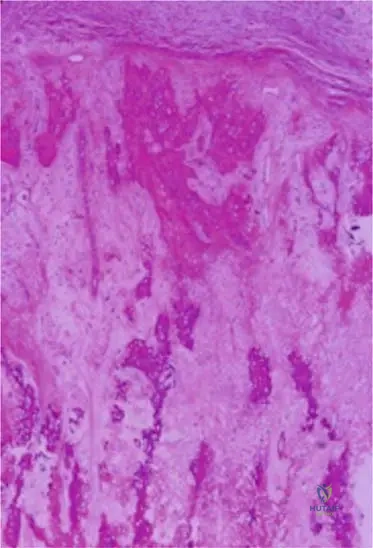

A 19-year-old male undergoes a biopsy of a suspected bone tumor. Histopathological examination reveals malignant cells consistently producing bony matrix (osteoid). The cells are pleomorphic, and mitotic figures are often present. These findings are characteristic of which type of osteosarcoma?

Rationale: Classic osteosarcoma pathology consistently shows malignant cells producing bony matrix (osteoid). The cells are pleomorphic, and mitotic figures are often present, indicating a high-grade malignancy. Parosteal osteosarcoma pathology is typically low-grade with little cytologic atypia, and periosteal osteosarcoma often shows chondroid matrix interspersed with osteoid.

A 16-year-old male undergoes biopsy of a destructive lesion in his distal femur. The pathologist reports findings of malignant cells producing bony matrix (osteoid), pleomorphism, and frequent mitotic figures. Which type of osteosarcoma does this pathology MOST strongly suggest?

Rationale: Classic (conventional) osteosarcoma pathology consistently shows malignant cells producing bony matrix (osteoid). The cells are pleomorphic, and mitotic figures are often present. This description aligns with the biopsy findings and the provided image (Fig. 8.75 a, b) of conventional high-grade osteosarcoma. Parosteal osteosarcoma is low-grade with little atypia. Periosteal osteosarcoma has chondroid matrix and mild atypia. Low-grade central osteosarcoma is a distinct entity not described in the text, but the features here are high-grade. Osteoblastoma is a benign bone-forming tumor.

A 12-year-old male presents with a rapidly expanding, painful mass in his proximal humerus. Imaging reveals a highly destructive lesion with large lytic areas. Biopsy reveals malignant spindle cells and osteoid, along with prominent blood-filled spaces. This microscopic appearance is characteristic of which variant of osteosarcoma?

Rationale: The image (Fig. 8.78) and its caption describe "Photomicrograph of telangiectatic osteosarcoma. Note malignant spindle cells and osteoid and associated blood-filled spaces." The clinical presentation of a rapidly expanding, destructive lesion with large lytic areas is also consistent with this aggressive variant. Parosteal and periosteal osteosarcomas have distinct features. Conventional osteosarcoma is a general category, but telangiectatic is a specific variant. Chondroblastic osteosarcoma would have a predominant chondroid component.

Question 41